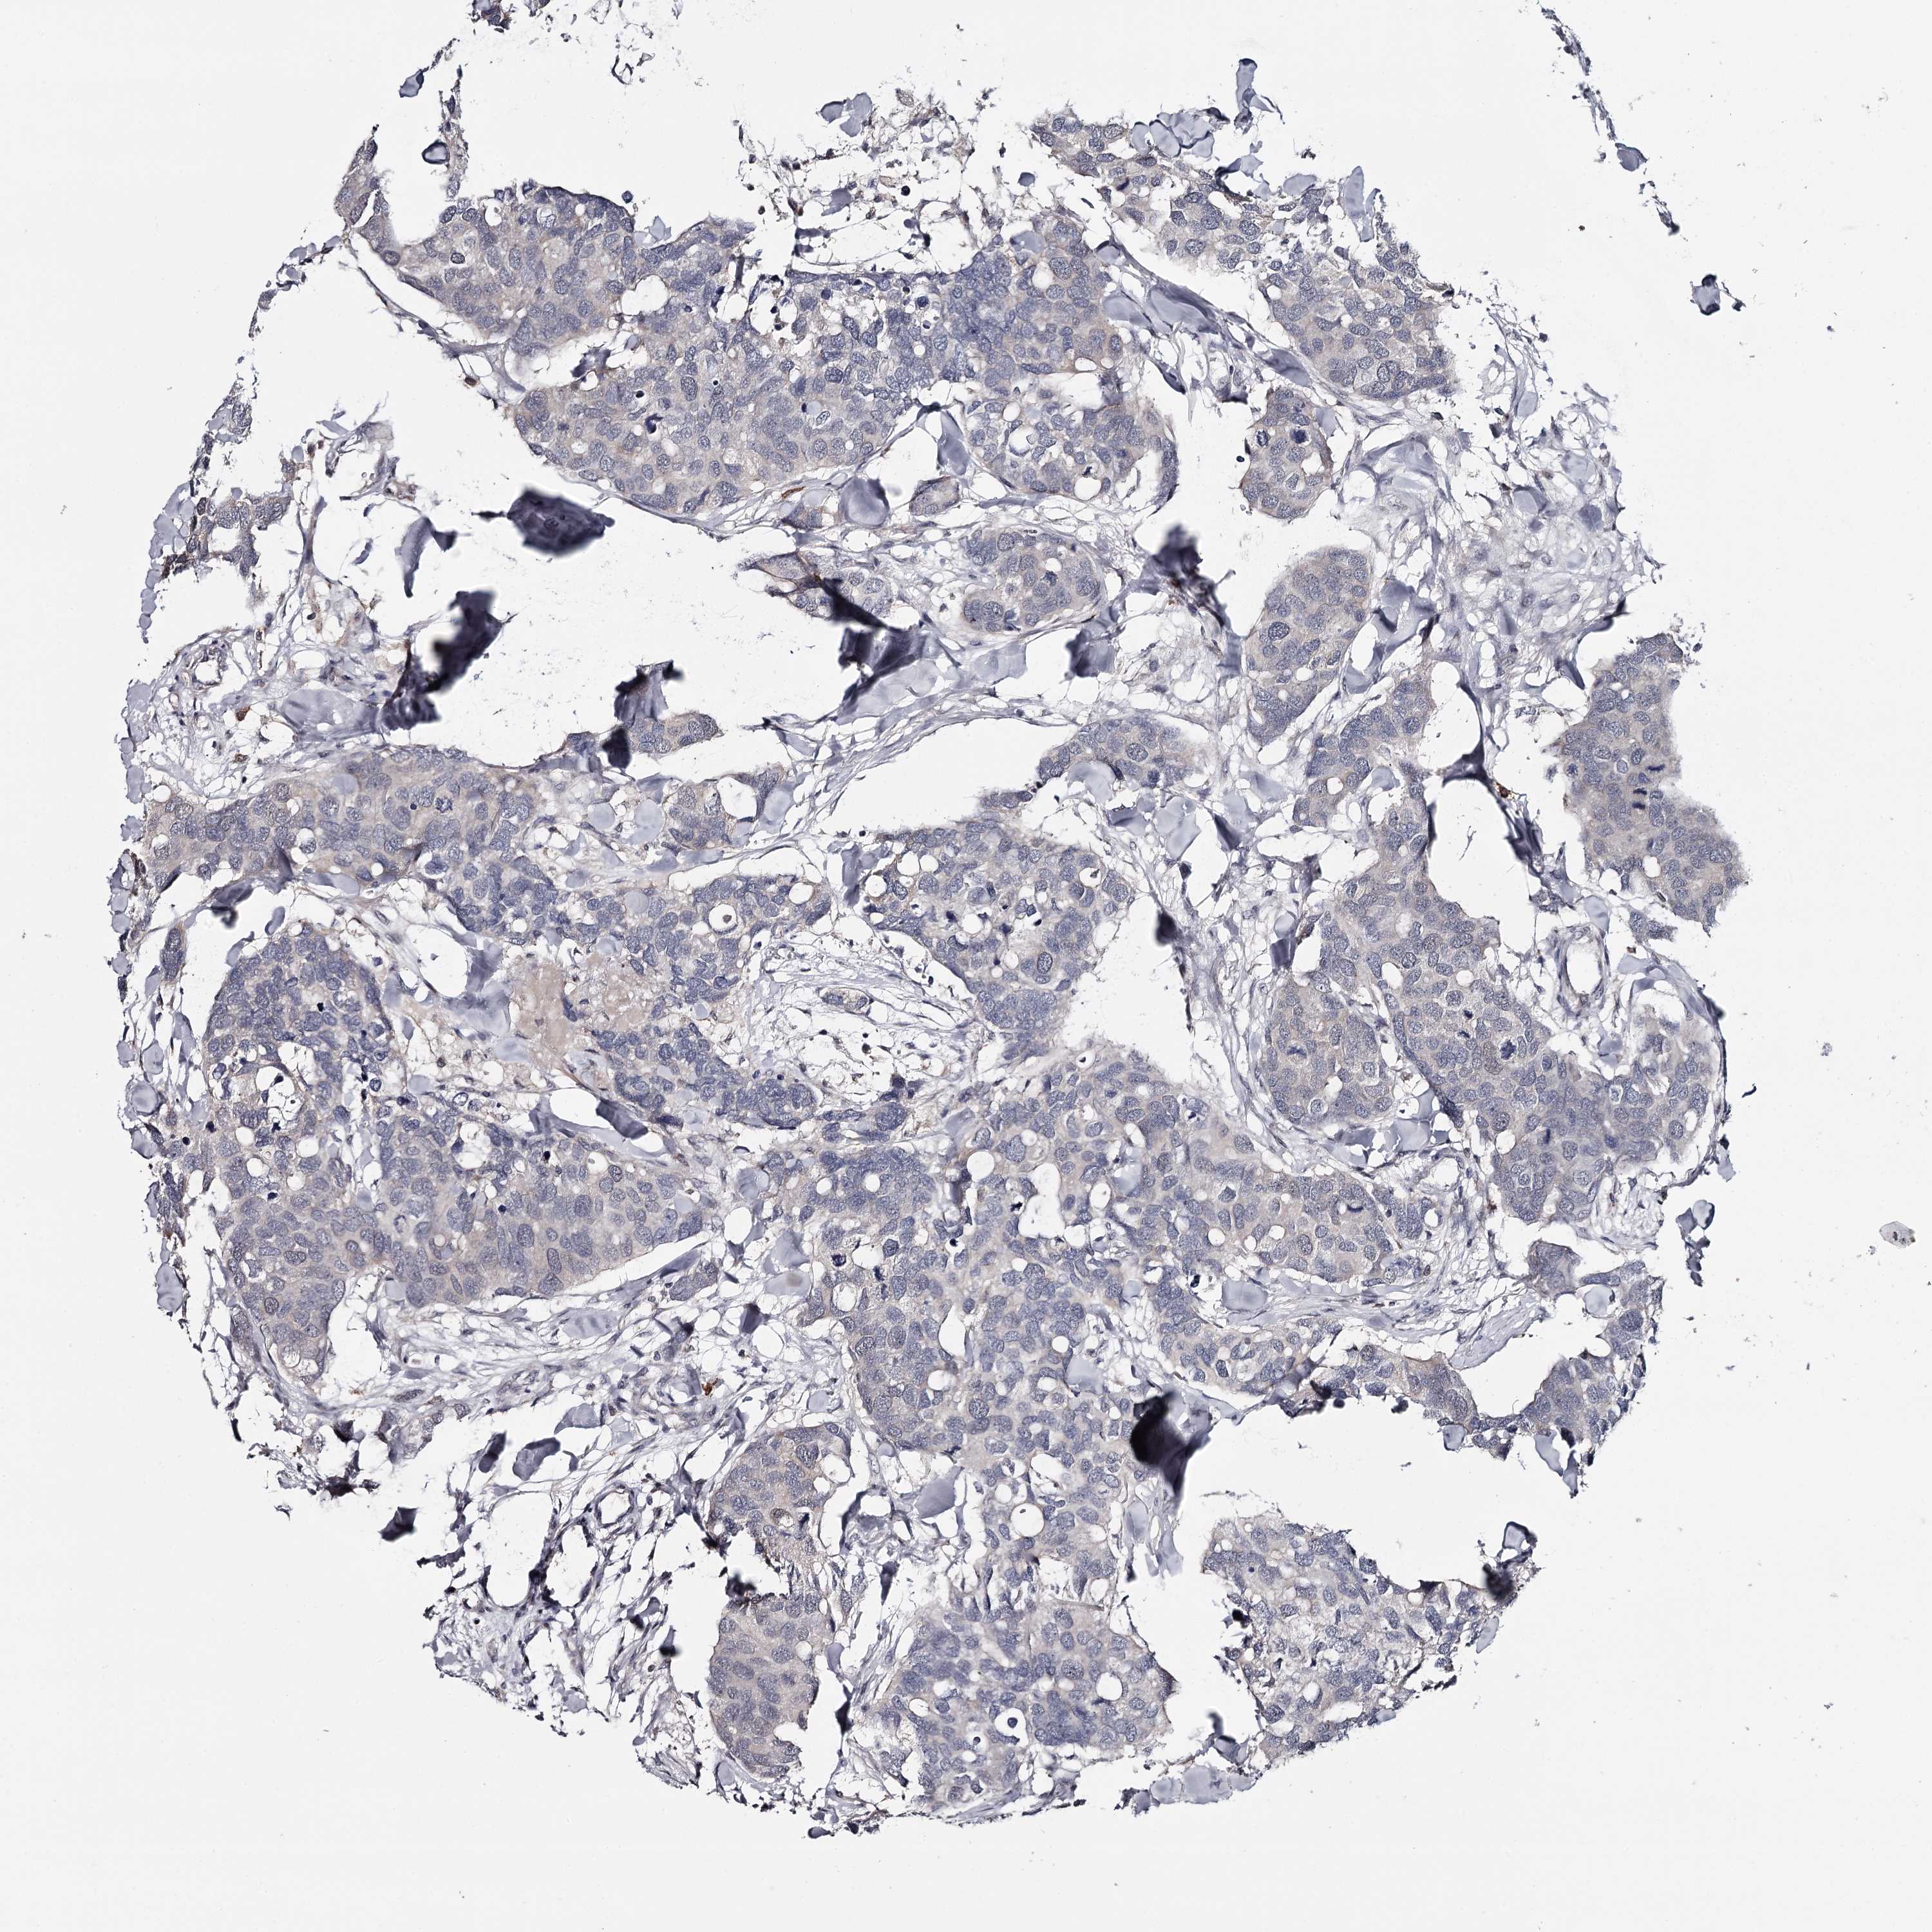

BRCA TCGA BRCA VALIDATION PROTEIN EXPRESSION

ANTIBODIES

AND

VALIDATION